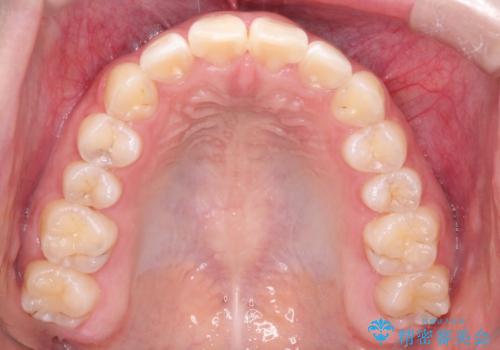

インビザラインによる出っ歯の非抜歯矯正

- 前歯が出ているのを主訴に来院されました。

上の前歯が前方に傾斜しており、上の前歯と下の前歯が接触していない状態でした。

上の奥歯を後方に移動させて、前歯を引っ込める計画としました。

しっかり使っていただけたので、スムーズに治療を終了することができました。